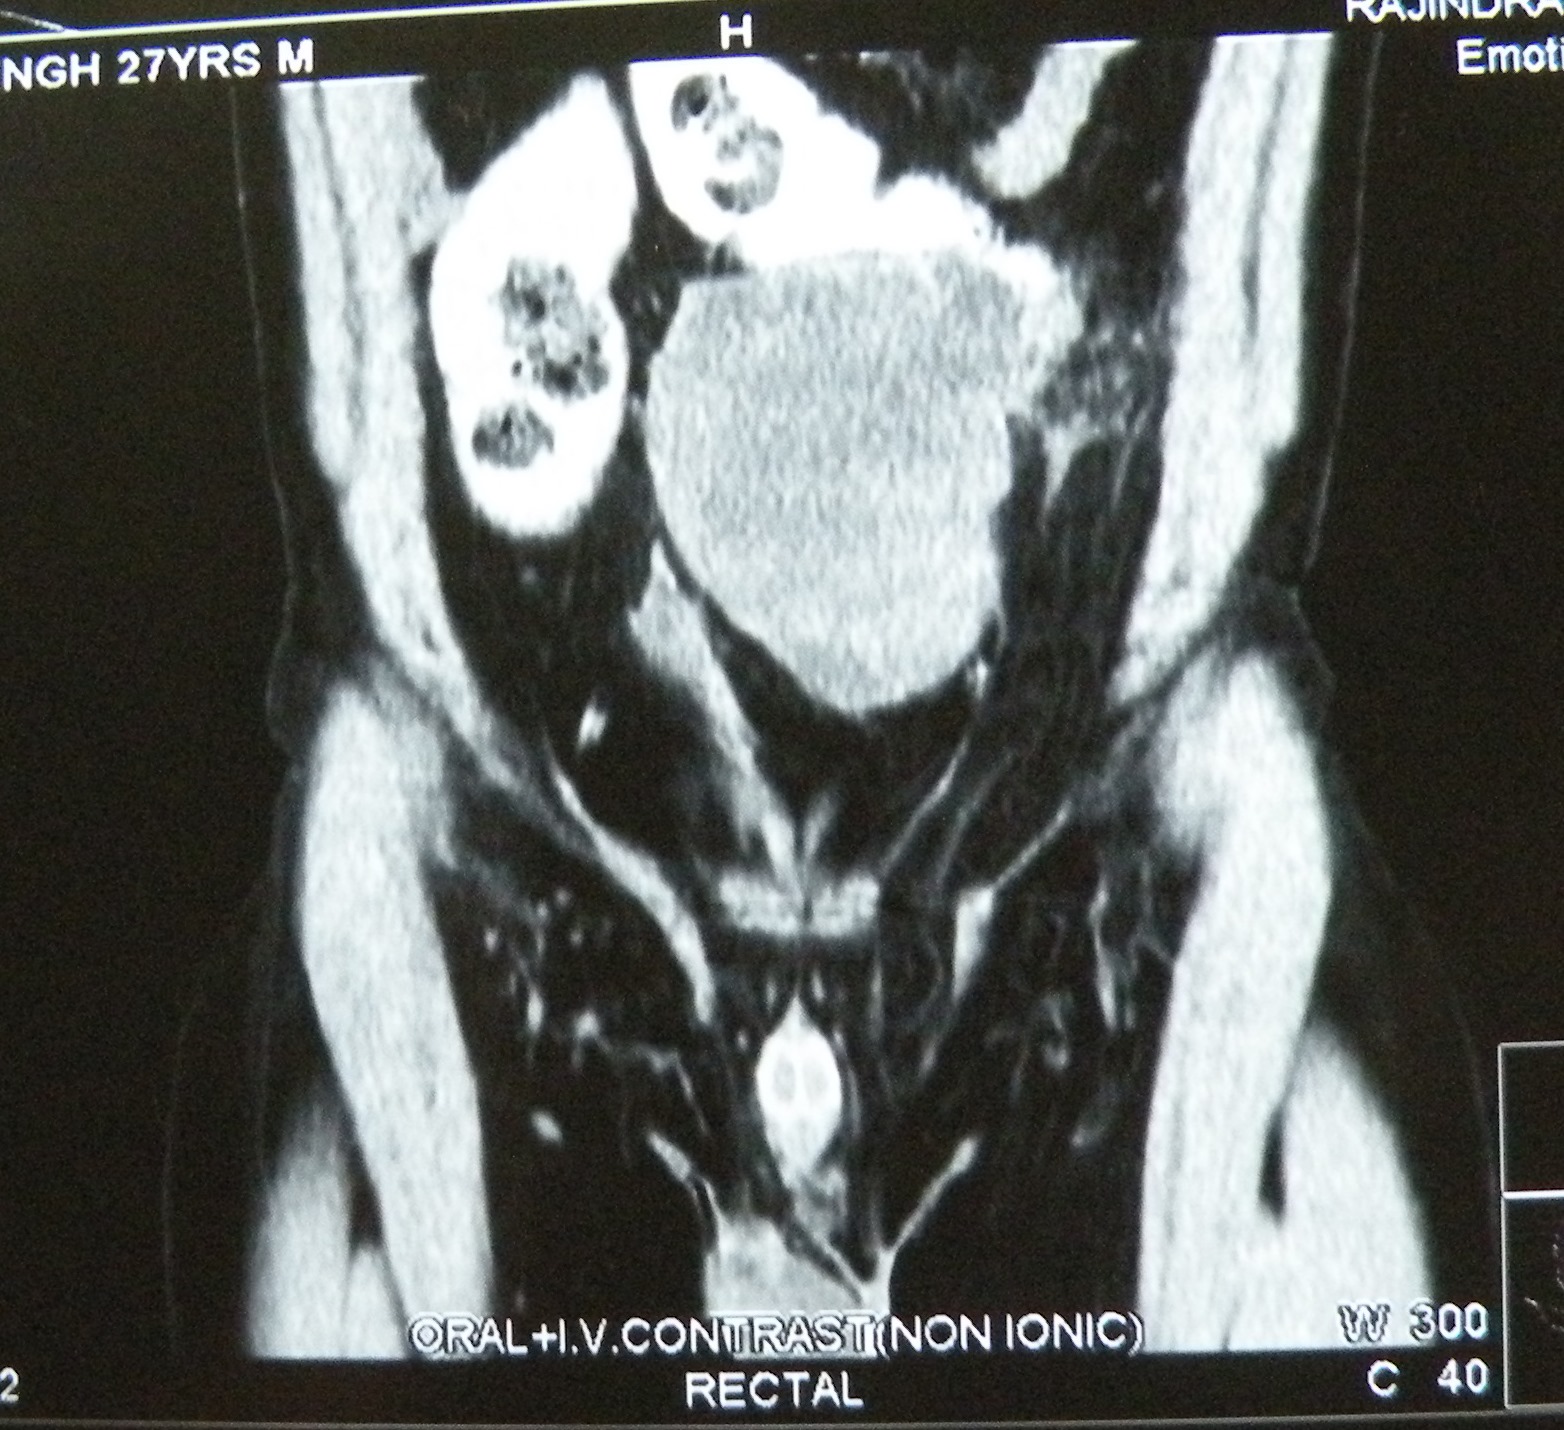

A 27 yeas old male, HCV positive, presented with a mass (15 cm across) in the left lower abdomen, and found to have an undescended testis on examination. AFP and HCG grossly elevated. At exploration, the big tumour was found to be adherent to the sigmoid colon, which had to be resected along with the tumour.